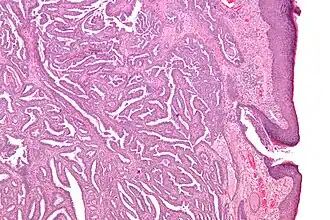

Micrografia de um adenoma do mamilo.

Adenoma do mamilo é um tumor da mama benigno e raro. Trata-se de um papiloma intraductal que surge nos ductos lactíferos do mamilo.[1] São mais comuns nas mulheres entre os 30 e 40 anos,[2] embora possam também ocorrer em homens.[3] Podem ocorrer em qualquer idade, incluindo na velhice, adolescência[4] e infância.[5] Podem ser detectados por palpação na forma de um nódulo por baixo do mamilo ou da aréola e chamar à atenção devido a dor no mamilo, ulceração, inchaço ou corrimento.[2]